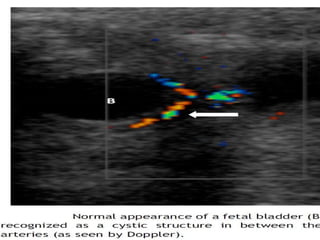

Renal Physiology Urine formation- first seen at the 5-8th week. Urine output  5 cc/h at the 20th week  50 cc/h by the 40th week. Bladder : visualized by  10-14th week  Bladder capacity  10 cc at the 30th week to 50 cc at term Br J Obstet Gynaecol 1977;84:205 .

Doppler Ultrasonography  Based  on the fact that obstruction causes an increase in intrarenal arterial resistance resulting in a relative reduction in diastolic flow compared to systolic flow. Use for the evaluation of renal obstructive disorders  currently controversial and not widely utilized.